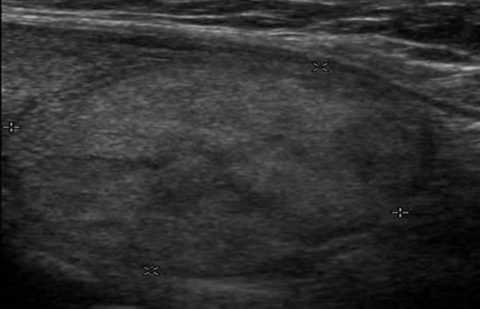

Интранодулярный кровоток

Термин «интранодулярный» также слагается их основ двух латинских слов, — intra (внутрь) и nodus (узел).

Отличительными особенностями этого типа васкуляризации являются:

- отсутствие либо незначительное количество кровеносных сосудов в стенках новообразования;

- хорошее кровоснабжение, а значит, обильное питание тканей внутри узла.

Статистические данные говорят о том, что 20% новообразований с таким типом кровоснабжения являются злокачественными. А при отсутствии у них капсулы и наличии гипоэхогенности, вероятность такого неблагоприятного развития возрастает еще на 10%.

Новообразование в щитовидке с интранодулярным кровотоком

Уточнение диагноза проводится за счет выполнения тонкоигольной аспирационной биопсии (ТАБ).